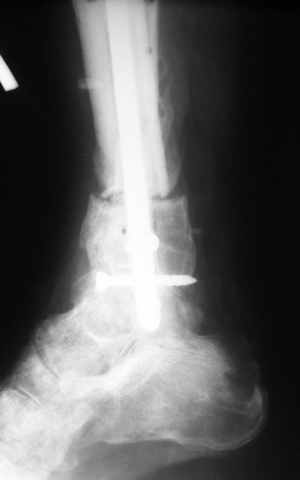

AO Principles of Fracture Management (2000 г.). Прочитав эти доступные книги (ссылки на них выкладывали на форуме не раз) и сделав пару лоскутов в морге можно смело делать эту операцию у живого пациента. Кстати у нас на следующей неделе планируется подобная операция для закрытия раны на пятке. Пусть доктора приезжают, поделимся своим скромным опытом. (рис. 1 , 2, 3 [извините, не успели отмыть кожу от иода], 4)

Больному выполнена резекция малоберцовой кости, ВХО раны, сближение отломков. Резекция м\б через отдельный разрез. После ВХО компрессия в аппарате, края раны сближены наводящими швами (без натяжения).

В случае гладкого заживления раны, при условии положительного решения вопроса с металлом, планируем перемонтаж аппарата Илизарова, дополнительную резекцию дистального отломка, выведение полокости голеностопного сустава в правильное положение (см. боковую Р-грамму), одномоментно остеотомия большеберцовой кости. После восстановления длинны голени, по всей видимости, артродез голеностопного сустава.

Рентгенограммы прилагаются. Фото местного статуса выложу в ближайшее время.

Мы обычно не фиксируем малоберцовую кость. Просто стараемся сопоставить ее концы за счет хорошей репозиции. В представленном случае имеется некоторое смещение дистальных фрагментов кнаружи, и, как мне кажется, ротация их вместе со стопой кнутри (ротация хорошо заметна на прямом снимке по форме таранной кости и на боковом по соотношению отломков малоберцовой). Если это действительно так, то это несложно сейчас постепенно устранить в аппарате. И тогда концы малоберцовой кости будут находиться поближе друг к другу.